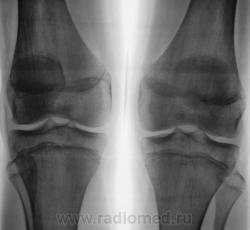

Женщина. 61 год. Вес 120 кг. Жалобы на боли и "хруст" в коленях. Рентгенологически - двусторонний артроз 3-й степени с наличием "вакуум-феноменов" в области внутренних менисков, большей выражености слева.

Сравнительная характеристика - в положении стоя наружные суставные щели гораздо шире, Х-образные конечности, ось нагрузки на внутренние отделы; в положении лежа уменьшаются. В положении лежа"соскальзывание" голеней наружу меньше. Внутренние суставные щели в положении лежа едва шире, очевидно сказывается резкое истончение мениска и хрящей со значительной потерей эластичности. Метрические показатели пока не оценивал. КАк поступить - мерить? тогда как лучше, дабы стандартизировать подход?